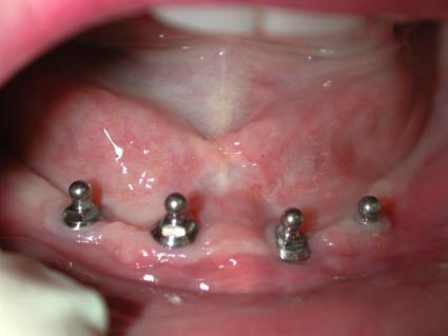

Endosteal implantlar - bu implantlar, cerrahi yöntemle, çene kemiğine direkt olarak implante edilirler. Çevredeki dişeti dokusu iyileştikten sonra, orijinal implanta bağlantı sağlayacak materyali takmak için ikinci bir operasyon gerekir. Son olarak, yapay diş (veya dişler) tek başına veya köprü ya da protez üzerinde grup halinde implanta takılır.